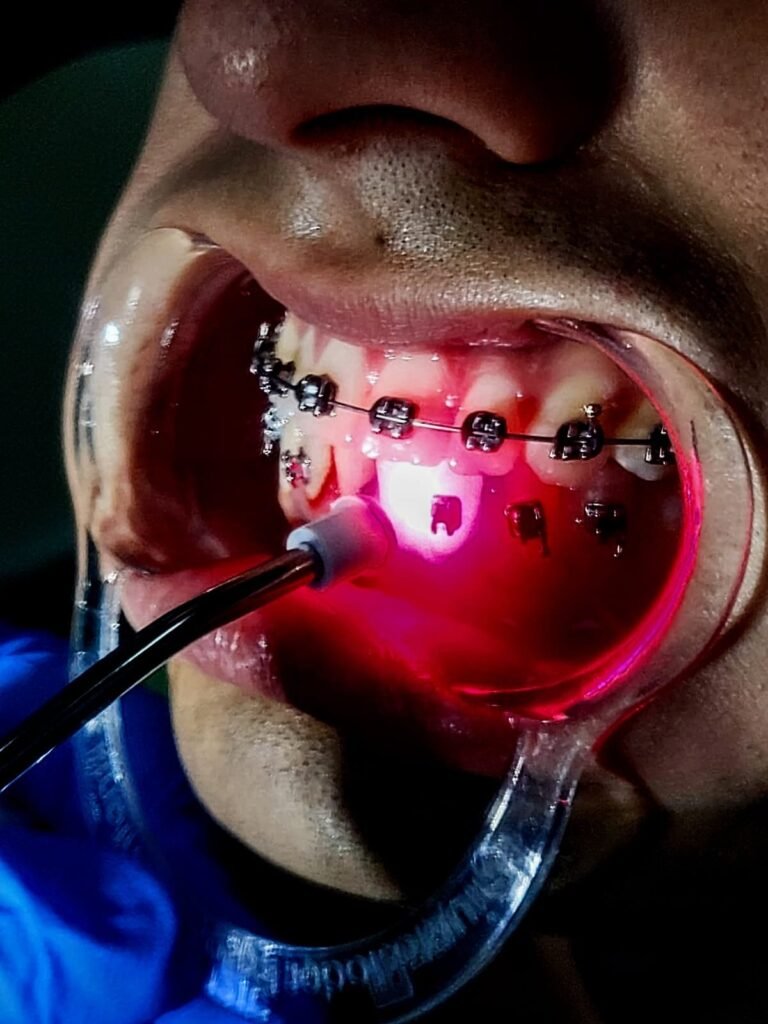

Terapias Complementarias

Uso de láser terapéutico para reducir dolor, acelerar la cicatrización y potenciar los resultados odontológicos.